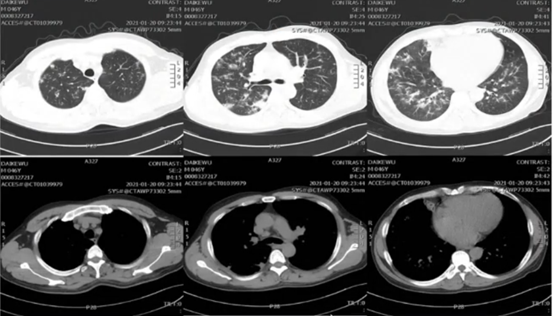

• 肺部+全腹部+肠系膜上动脉增强CT:①网膜、系膜、左肾前筋膜、侧椎筋膜增厚模糊,盆腔少许积液;②胆囊炎,肝内钙化灶;③双肺支气管血管束增多,多发斑片状、结节状密度增高影,边缘模糊,部分可见晕征,右中上肺小叶间隔稍厚(图2)

2.jpg

图2  2021年1月20日患者本院门诊胸部CT